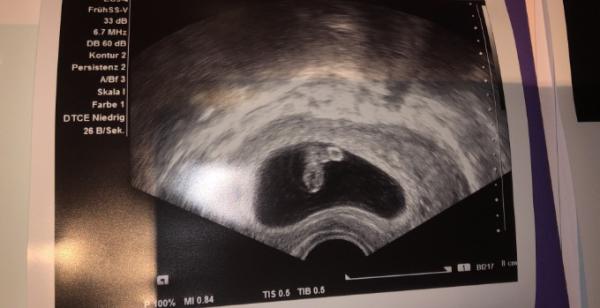

Hallo ihr lieben Juni-Baby-Mamas. Ich bin Christin und 35 Jahre alt und bereits das 2. mal in diesem Forum. Leider war der erste Ausgang nicht ganz so gut. Mein Sohn kam am 8.11.2019 mit einer fehlbildung der Luft- und der Speiseröhre durch einen Kaiserschnitt in der 36.ssw auf die Welt und verstarb auf Grund der schlimmen fehlbildung kurz nach der Geburt. Kurz vor seinem 1. Geburtstag durfte ich endlich positiv testen und bin jetzt bei 7+5. für uns beginnt natürlich jetzt eine wahnsinnig aufregende Zeit mit vielen Untersuchungen und natürlich großer Angst, dass unserem Regenbogenbaby irgendetwas passiert. Jeder Tag ist begleitet von Höhen und Tiefen. Aktuell bin ich erstmal krank geschrieben, da die psychische Belastung in den letzten Tagen doch nicht ohne war. Sorry für den langen Text, aber ich wollte euch gern an unserer Geschichte teilhaben lassen und freue mich auf die nächsten Monate mit euch! Lg und euch allen einen guten Start ins Wochenende